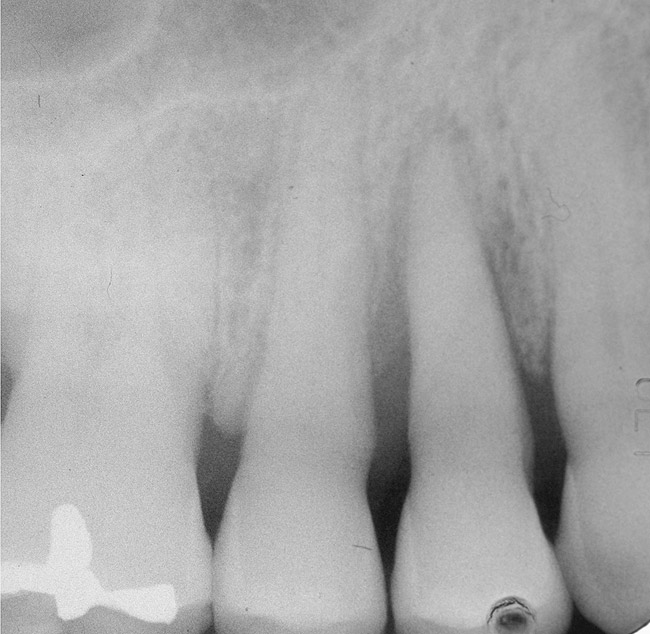

Figure 3   Radiographic appearance of the repaired osseous defect seen in Figure 2 approximately 6 months after extraction and immediate bone grafting of the socket. Note the radiographic repair of the bone on teeth Nos. 4 and 6.

Figure 3

Figure 4  Clinical photograph showing preservation of the ridge seen in Figure 3.

Figure 4

To meet the needs of the new paradigm, treatment techniques have evolved for bone preservation. Figure 1 shows a case in which tooth No. 5 had advanced bone loss and the treatment option was to save it. The patient did not opt to have this treated, however. Figure 2 shows the same area approximately 18 months later when the advanced bone loss was also affecting the adjacent teeth. Traditional treatment—extraction of this tooth—would have led to a significant hard- and soft-tissue defect. Use of the alternative treatment—grafting of the socket at the time of extraction19,20—preserved the hard and soft tissue (Figure 3 and Figure 4). Grafting the socket to minimize postextraction ridge shrinkage is a much more conservative approach than performing ridge augmentation after extraction,21 which would have been required if the socket grafting had not been done in conjunction with the extraction.